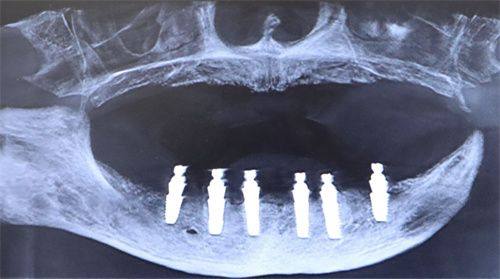

医院的设备也十分精良,引进了国内外精良的口腔诊疗设备,如数字化口腔全景机、种植机等,这些设备能够为患者提供更精细的诊断和更有效的治疗。而且医院的环境舒适宜人,采用了现代化的装修风格,让患者在就诊过程中感受到轻松和舒适。